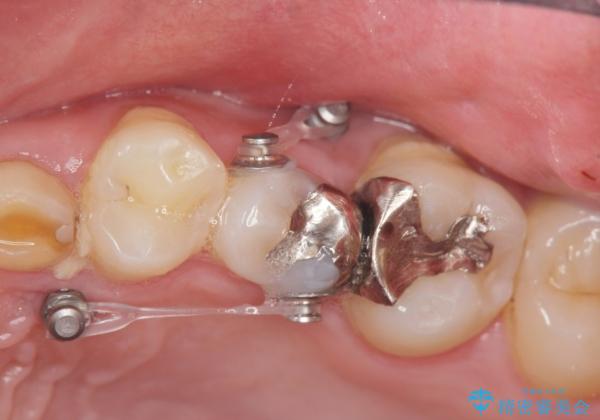

- ねじれてしまっている奥歯の矯正治療、銀歯のセラミック治療を求めて来院されました。

銀歯を外す前に部分矯正治療を行うことで歯のポジションを調整したのち、セラミック治療を行います。

90°ねじれてしまっていた歯を、矯正治療で治し、前後の歯の咬合関係も改善してしっかりと噛めるようになりました。